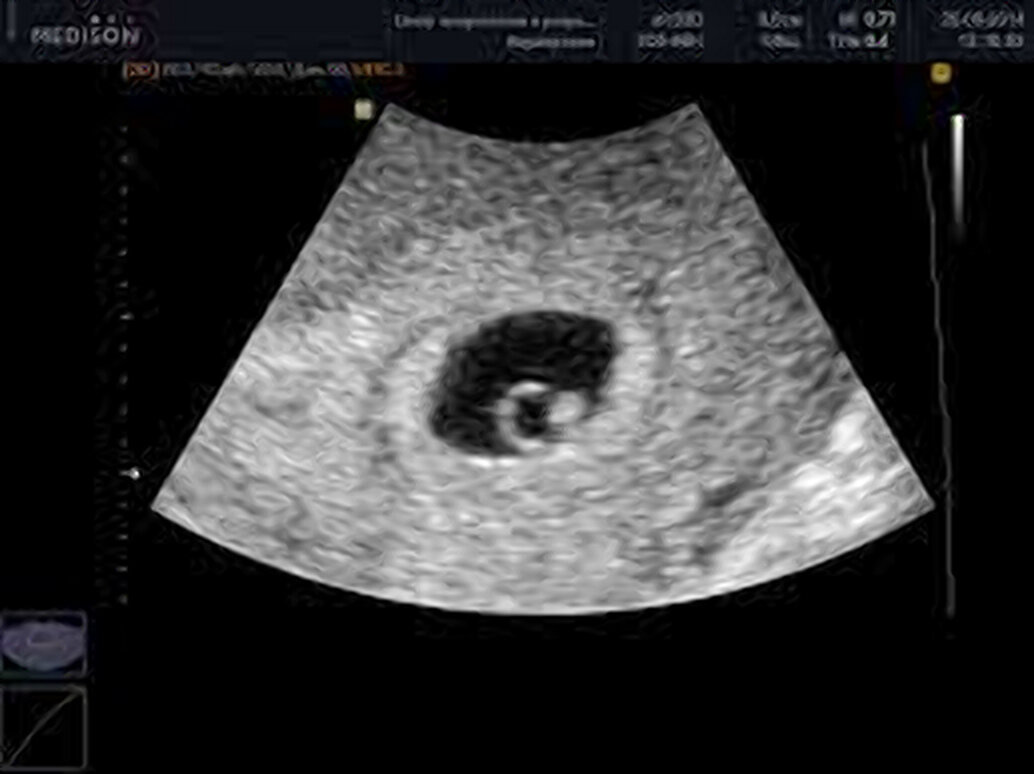

Так выглядит шестинедельный эмбрион на УЗИ

Наконец-то всё получилось! Тесты на беременность показали слабую вторую полоску уже на четвертый день после переноса эмбриона, и с каждым днём всё ярчали. Потом пришел положительный результат анализа на ХГЧ (хорионический гонадотропин человека), гормон, который вырабатывается плодными оболочками при беременности. Позади осталось и УЗИ, где уже можно было рассмотреть круглое плодное яйцо, маленькую камеру, похожую на пузырёк, в которой находится малюсенький эмбриончик, похожий на вытянутую бусинку, в центре которой пульсирует миниатюрное сердечко.